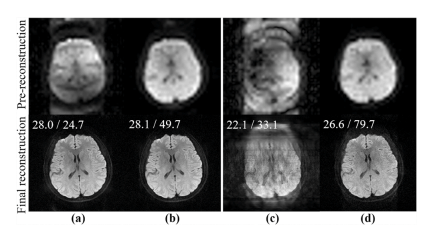

Fig. 9. Shot phase of 4-shot and 10-shot cervical spine DWI in Fig. 7. (a)-(d) are the MUSSELS, PAIR, pre-reconstruction, and final reconstruction of DONATE, respectively

图9:图7中4次激发和10次激发的颈椎弥散加权成像(DWI)的激发相位。(a)-(d) 分别是MUSSELS、PAIR、DONATE重建前以及DONATE最终重建的结果。